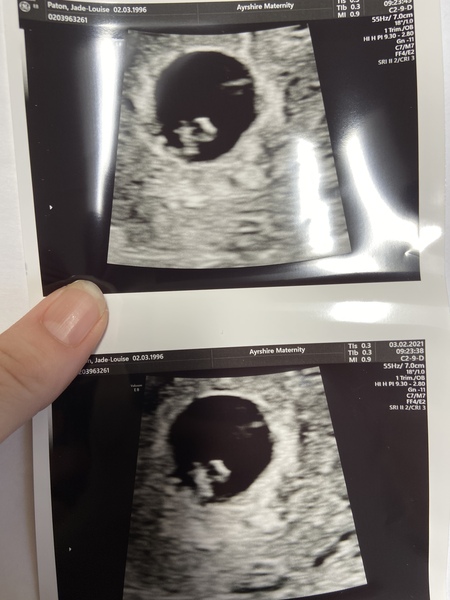

Well ladies after all that worrying and stress since I found out because of the cramps etc I’ve been having. Just returned from my early scan and have a healthy little bean with a heartbeat